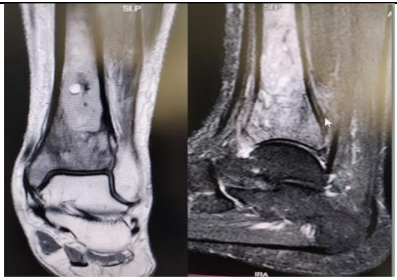

MR

MR imaging showed the presence of distal tibial 3*2*1 cm partially defined cyst, with a narrow zone of transition with heterogenous enhancement in the surrounding bone marrow, cortical thinning and smooth periosteal elevation, suggesting a neoplastic etiology , no soft tissue or vascular involvement or skip lesions (figure2).

Figure 2: Magnetic resonance imaging of left distal tibia showing distal tibial osteolytic lesion with narrow zone of transition with surrounding medullar altered signal intensities with heterogenous contrast, periosteal elevation and thinning suggesting a neoplasm.

Figure 2